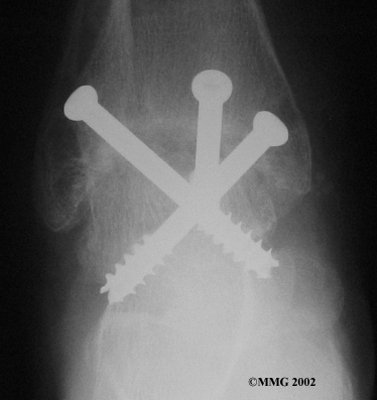

It is important when the surfaces are removed that the angles of the cut surfaces are correct. When the tibia is brought against the talus, the foot should be at a right angle to the lower leg. Once the cuts are made the bones must be held in place while they fuse. This can be done using large metal screws and metal plates if necessary. The screws are usually under the skin and are not removed unless they begin to rub and cause pain.

Inserting the screws

After ankle fusion, the physical therapists at FYZICAL Bradenton Central can help you learn to walk smoothly and without a limp. Although time needed for recovery varies among patients, an ankle brace will typically replace your cast after eight to 12 weeks. Your surgeon will take X-rays frequently to see if the bones are fusing together. You will probably need to use  crutches during the time you wear the cast. As the fusion grows stronger, you will begin to put more weight on your foot when walking.